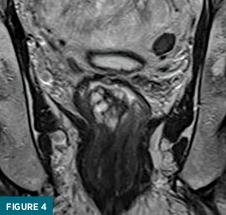

Coned-down T2-weighted axial (Figure 3) and coronal (Figure 4) MRI images demonstrated a polypoid 3.1 x 2.5 x 2.8 cm mass confined to the rectal submucosa with several T2 hyperintense cystic areas; this mass correlates with findings on prior CT and ultrasound. Postcontrast axial (Figure 5) and coronal (Figure 6) MRI images demonstrated a lack of enhancement in the cystic areas with overlying mucosal enhancement. There was no invasion of muscularis propria, and the overlying mucosa was intact. No abnormal lymph nodes were present in the pelvis. The patient underwent surgical excision of the mass for a definitive diagnosis.